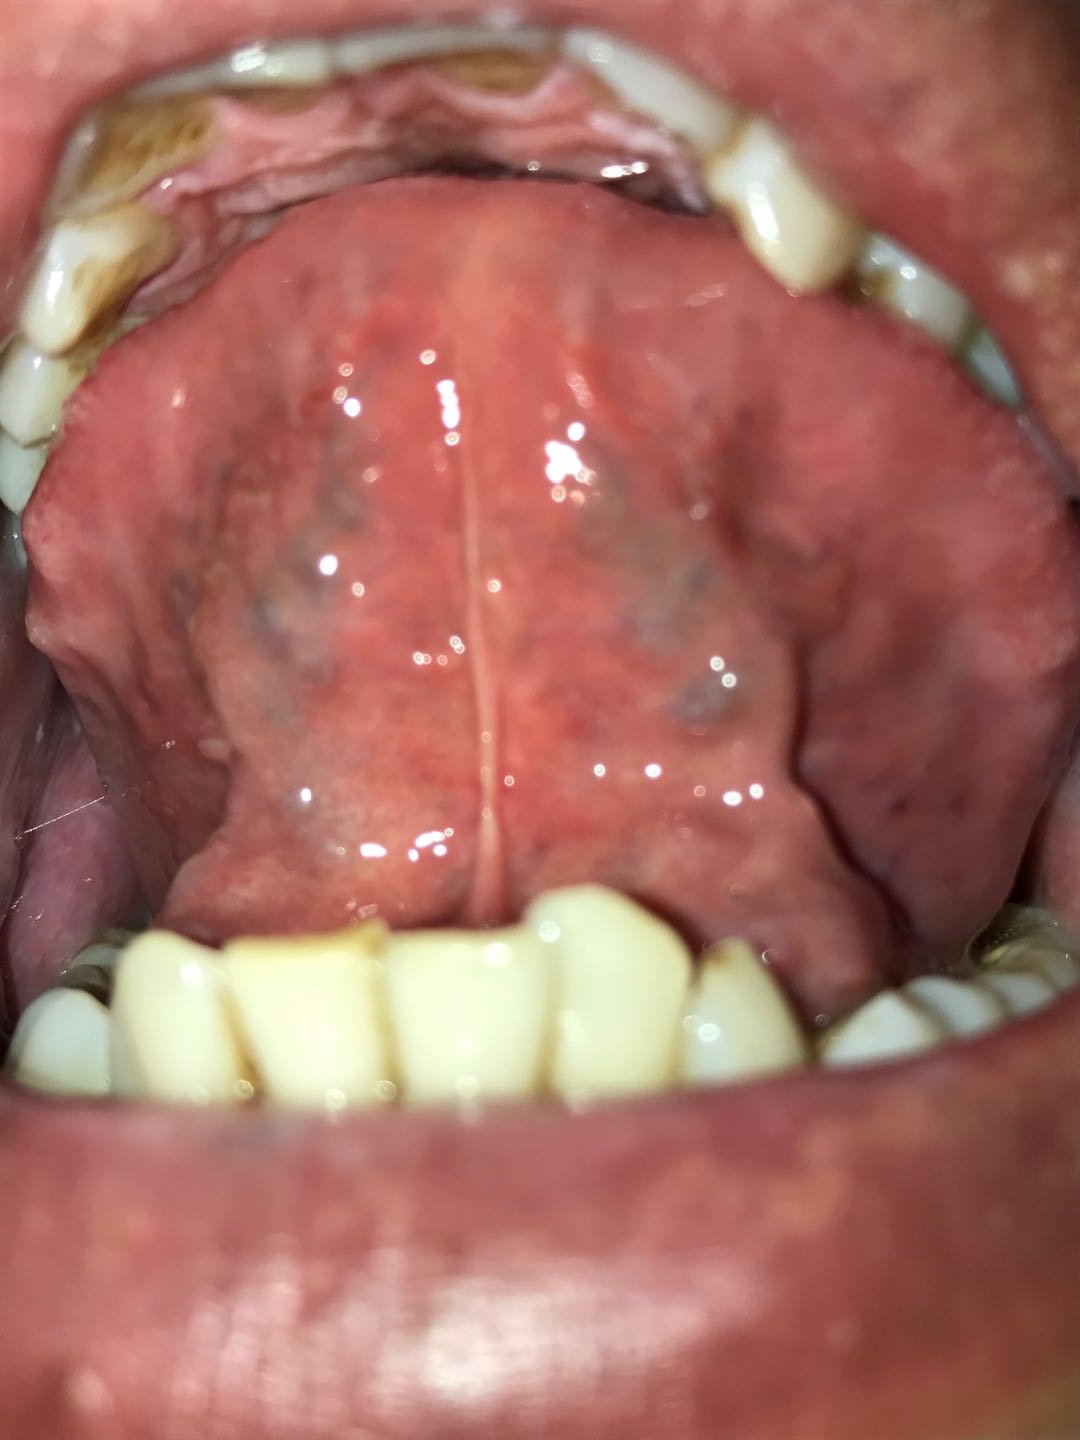

1、舌样没改变,晨起苔黄,中间有裂沟,边上有齿痕;

1、舌样根部还是黄厚,具体看下图:

一些关于便于正确诊断的建议:舌象最好是在自然光照射舌头然后拍照,注意别挡住光。因为照相机白平衡的原因,阴天或者其他颜色灯光容易出现错误的颜色。此外,拍照前不要抽烟,若抽了,最好漱口,以免影响颜色。最后,吃过一些有染色效果的食物或者水果饮料等,舌会被染色,所以要注意这些。最后,舌象只能反映最表面的现象,而不能反映实质,只有在一层层抽丝剥茧用药后才显现出来,论坛中醫道宗源发的好几个疑难病的案例中就是如此。所以也不要太过于在乎这个。

1、舌照都是晨起后不做任何事在洗手间开着灯手机在曝光和不曝光状态下各照一张;